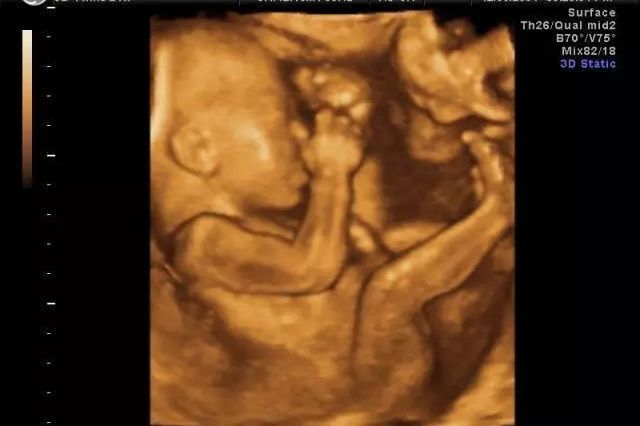

可以的,都是进行胎儿排畸检查的,三维彩超和四维彩超的区别就在于在一个“时间维”,也就是说,三维彩超是图片,四维彩超是录像,四维立体效果比三维更好,而且还可以清晰的看见宝贝在妈妈肚子里的一连串的动作。做三…